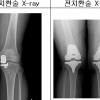

‘망가진 무릎’, 고장난 곳만 인공관절 대체하면 ‘끝’